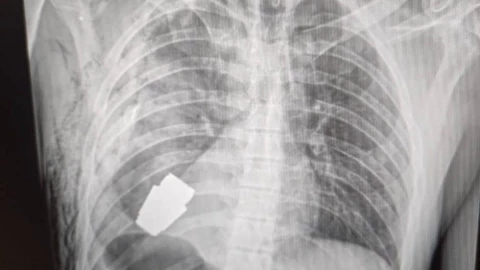

La viceministra de Defensa de Ucrania, Hanna Maliar, difundió algunas fotografías de la radiografía del soldado con la granada incrustada en el pecho y después otra donde aparece uno de los cirujanos con el explosivo en la mano.